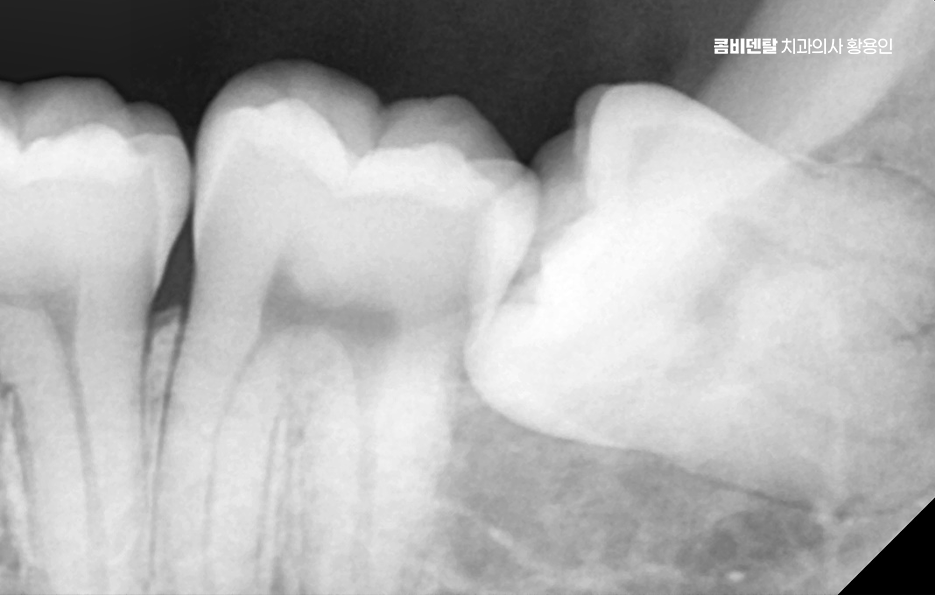

출처 아카이브 열기완전매복사랑니라는 단어 자체가 참 낯설게 느껴졌어요, 처음에는 그게 무슨 말인지조차 몰랐고, 단순히 사랑니라는 건 그냥 어금니 맨 끝에 나중에 나오는 이 정도로만 알고 있었어요 누구나 한 번쯤은 뽑는 거니까 나한테도 언젠간 그런 일이 생기겠지 하면서도, 사실 딱히 깊이 고민해본 적은 없었어요, 그런데 어느 날 왼쪽 아래 턱 깊숙한 곳이 묘하게 욱신거리고, 무언가 불편한 느낌이 계속되더라고요, 딱히 부어오르거나 겉으로 드러난 문제는 아닌데, 먹을 때마다 이상하게 한쪽으로는 씹기 싫고, 가만히 있을 때도 잇몸 깊은 곳에서 묵직한 압력이 느껴지는 기분이었어요, 그게 몇 주째 반복되니까 이제는 그냥 넘길 수 없겠다는 생각이 들어서 치과에 가게 됐어요. 진료를 받고, 엑스레이를 찍고, 설명을 듣는데, 그제야 알게 된 게 바로 완전매복사랑니라는 이름이었어요, 내 사랑니는 겉으로는 전혀 드러나지 않았지만, 잇몸과 뼈 안쪽 깊숙이 누운 채로 누워 있었고, 그것도 똑바로 난 게 아니라 옆 어금니 방향을 향해 비스듬히 자라고 있다는 것이었죠. 문제는 사랑니 발치도 까다로울 수 있고 주변 치아나 잇몸에도 영향을 줄 수 있다는 점이었어요

완전 매복사랑니는 보통 아래턱, 즉 하악의 뒤쪽에서 자주 발견되는데 위턱보다는 아래턱 뼈가 더 단단하고 구조적으로 복잡해서 발치 난이도가 더 높을 수 있으며 이 매복된 사랑니는 위치나 각도에 따라서도 발치의 난이도가 달라질 수 있었어요

여기에 더해서 신경과의 거리도 문제로 아래턱에는 하치조신경이라는 굵은 감각신경이 지나가는데 완전 매복사랑니의 뿌리가 이 신경과 가까이 위치해 있는 경우가 많아서 만약 발치 중 이 신경을 건드리거나 손상이 생기면, 입술이나 턱 끝 부위에 감각 이상이 생길 수 있어요.

완전매복사랑니 발치 그래서 무조건 바로 뽑는다고 되는 게 아니라, 사전에 정밀한 진단과 영상검사가 꼭 필요하며 일반적인 파노라마 사진 외에도 CT 촬영을 통해 신경과의 거리, 뿌리의 형태, 턱뼈의 두께 등을 정밀하게 확인해야 발치 계획을 안전하게 세울 수 있었어요.